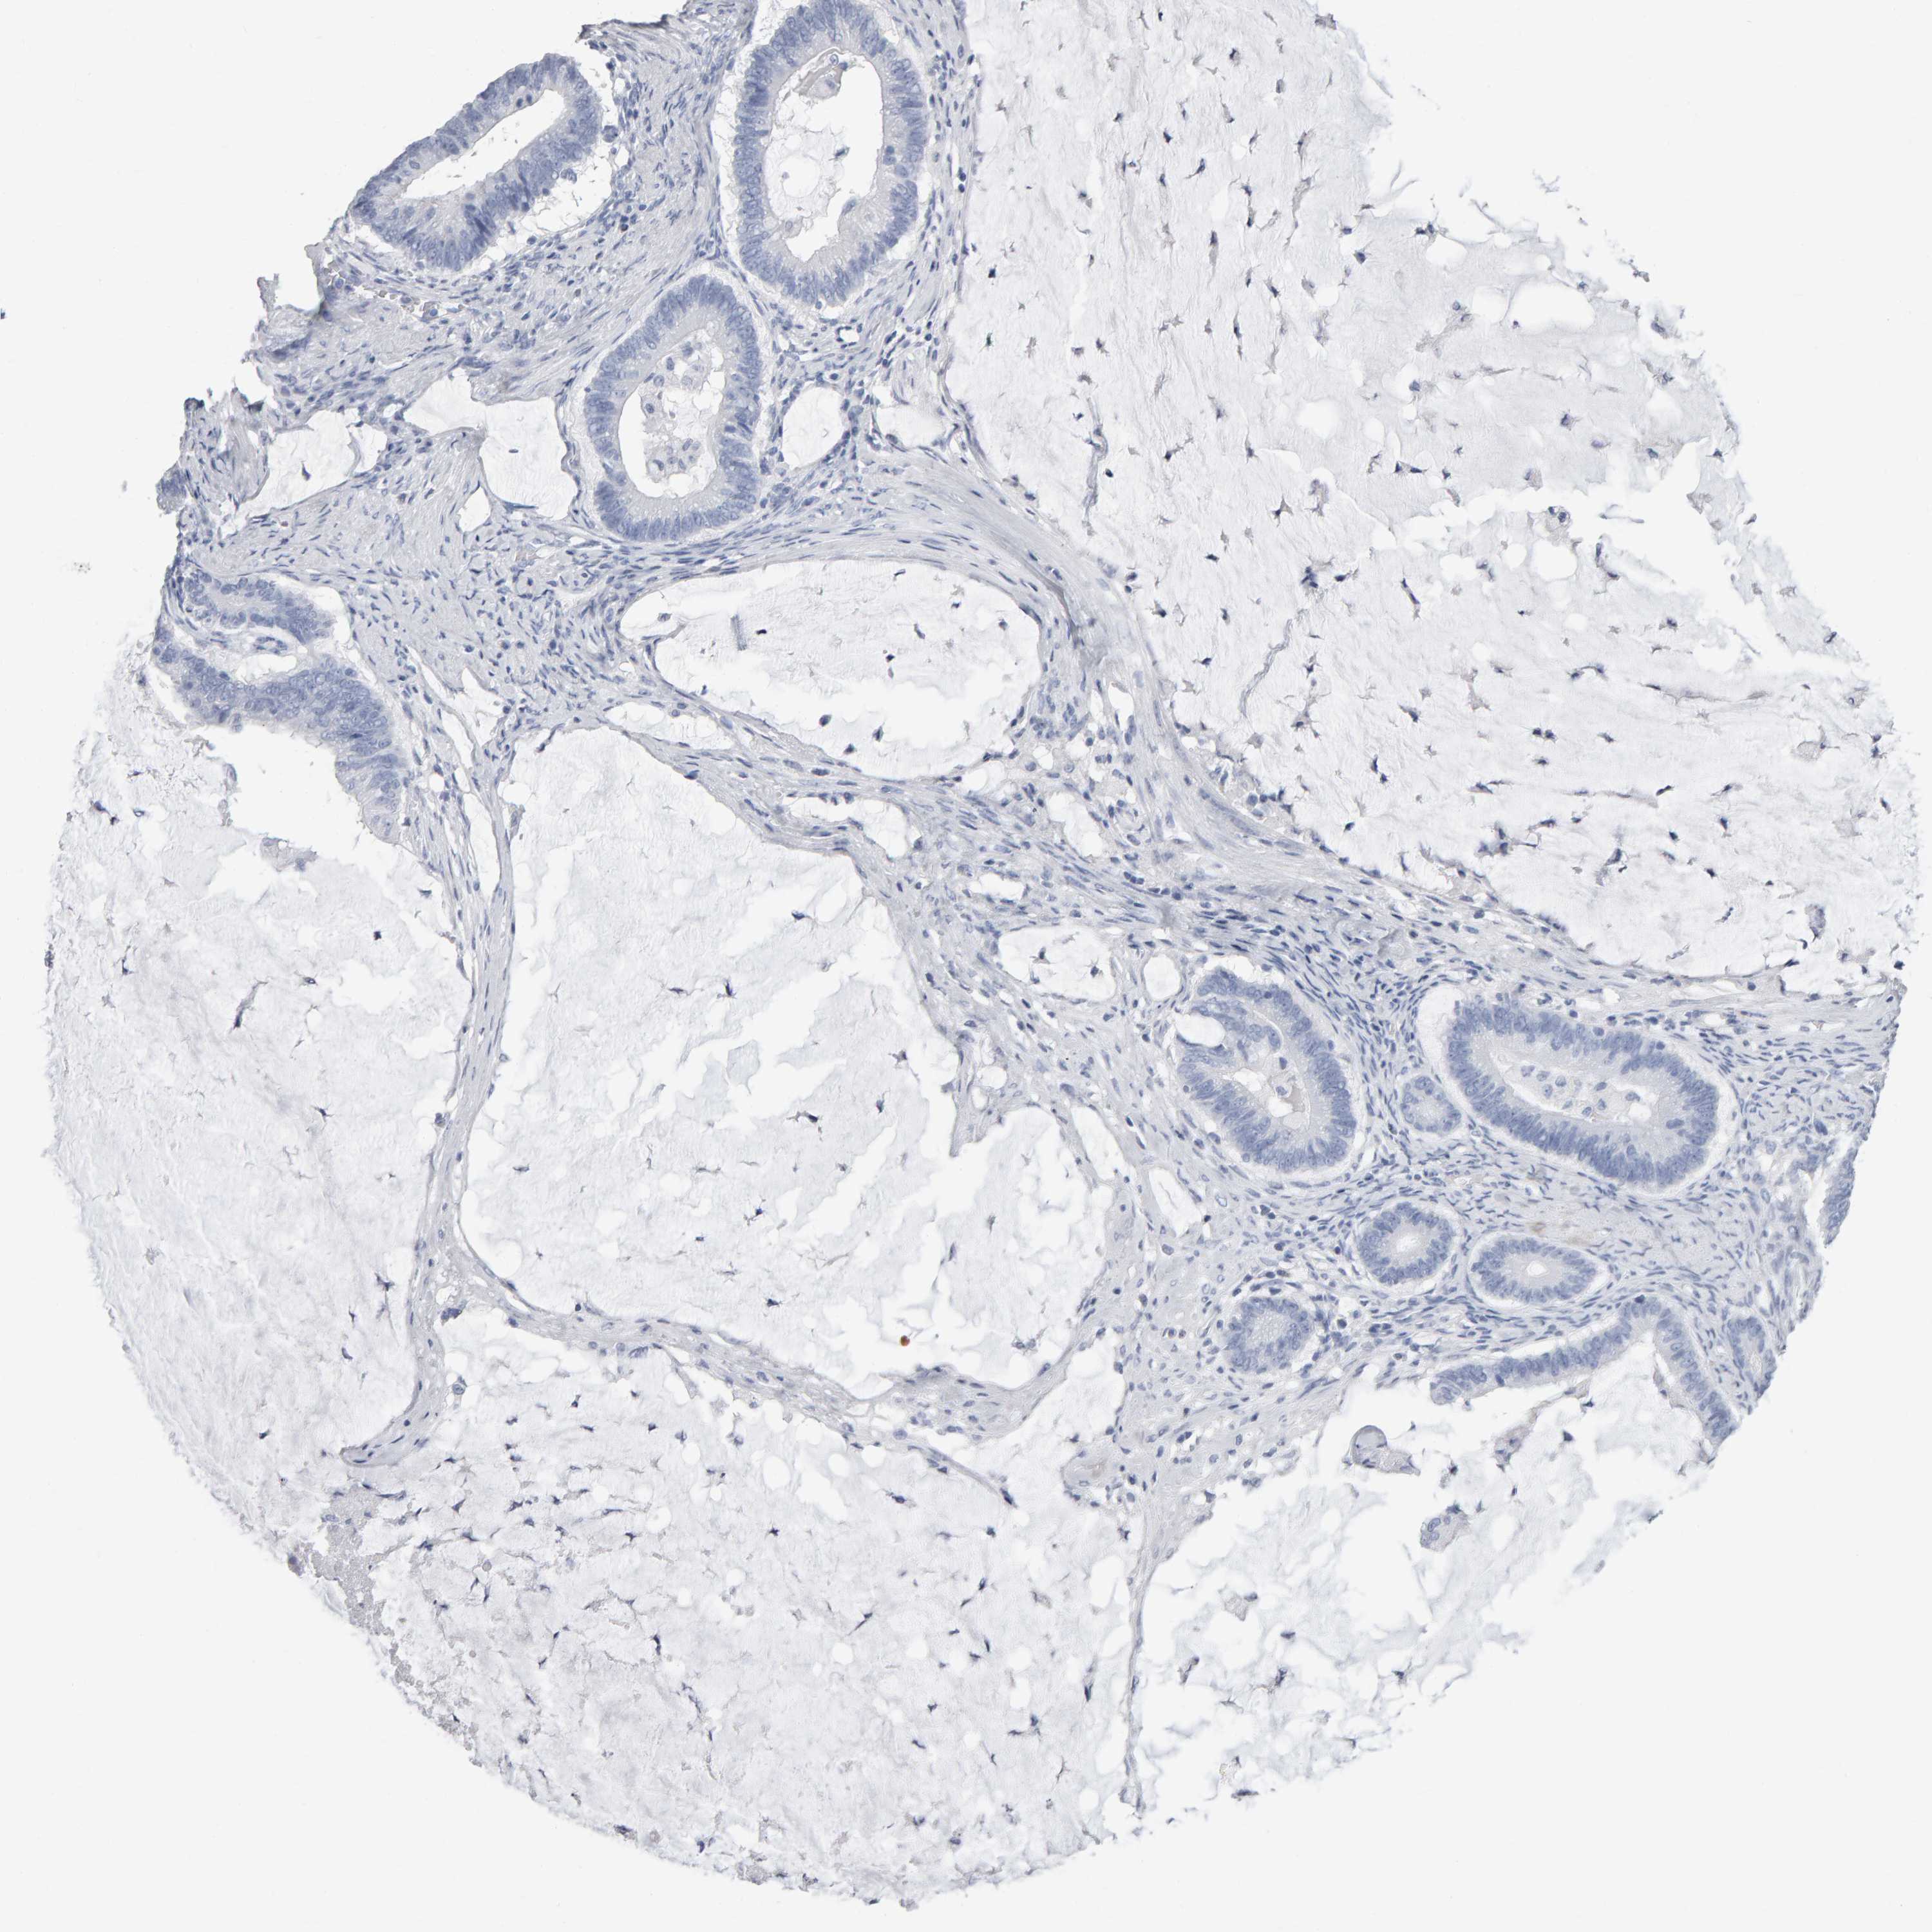

OVARIAN CANCER - Protein expressioni

A mouse-over function shows sample information and annotation data. Click on an image to view it in a full screen mode. Samples can be filtered based on level of antibody staining by selecting one or several of the following categories: high, medium, low and not detected. The assay and annotation is described here.

Note that samples used for immunohistochemistry by the Human Protein Atlas do not correspond to samples in the TCGA dataset.

Antibody stainingi

Antibody staining in the annotated cell types in the current human tissue is reported as not detected, low, medium, or high, based on conventional immunohistochemistry profiling in selected tissues. This score is based on the combination of the staining intensity and fraction of stained cells.

Each image is clickable and will lead to virtual microscopy that enables deeper exploration of all samples and also displays staining intensity scores, fraction scores and subcellular localization as well as patient and tissue information for each sample.

Antibody HPA023676

Staining

High

Medium

Low

Not detected

Intensity

Strong

Moderate

Weak

Negative

Quantity

>75%

75%-25%

<25%

None

Location

Nuclear

Cytoplasmic/membranous

Cytoplasmic/membranous,nuclear

Cystadenocarcinoma, serous, NOS

Carcinoma, endometroid

Cystadenocarcinoma, mucinous, NOS

Carcinoma, NOS